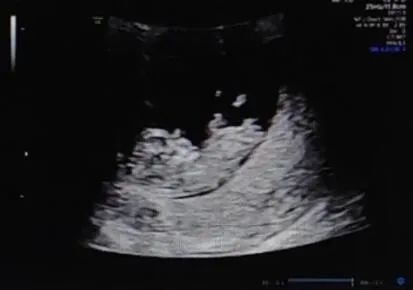

陈女士(化名),36岁,宫腔性不孕;2022年咨询试管婴儿助孕。

准备就绪移植囊胚,成功妊娠并“毕业”产检。